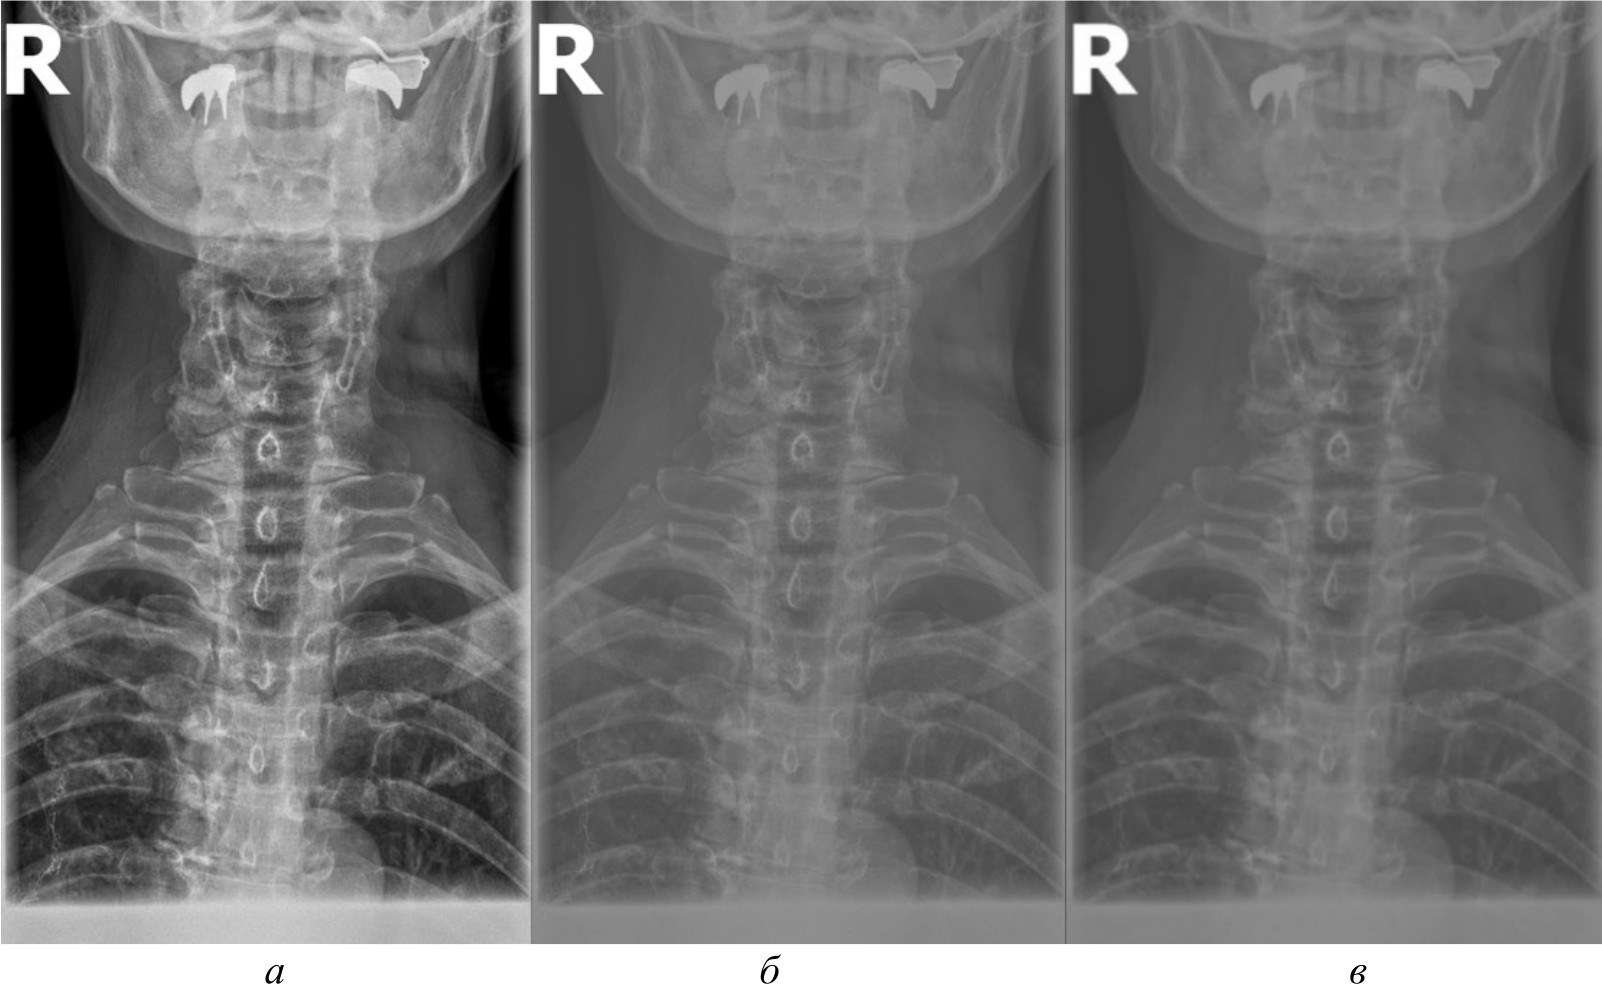

Автоматизированное распознавание таких ключевых анатомических ориентиров на рентгеновских изображениях представляет собой важную задачу, решение которой может повысить точность и скорость медицинской диагностики, обеспечив врачей объективной информацией для принятия решений. Компьютерное зрение способно автоматически локализовывать и идентифицировать анатомические структуры, измерять их размеры и взаимное расположение, а также выявлять отклонения от нормы, указывающие на наличие патологий. Однако недостаточное качество рентгеновских снимков, наличие помех, артефактов и неравномерностей может затруднять их восприятие системами компьютерного зрения. На рис. 1, а продемонстрирован рентгеновский снимок без предварительной обработки.

Рис. 1. Рентгеновский снимок без предварительной обработки (а); результаты работы детектора Harris на изображении без предварительной обработки (б)

Как видно на рис. 1, б, применение алгоритмов компьютерного зрения на необработанном изображении приводит к нечетким и неустойчивым результатам обнаружения ключевых анатомических ориентиров. Тем самым важной задачей, обеспечивающей эффективное применение алгоритмов компьютерного зрения, является разработка эффективных алгоритмов предварительной обработки изображений. Данные предварительной обработки, такие как улучшение контраста и устранение артефактов, служат основой для более точного и надежного анализа с использованием алгоритмов компьютерного зрения. Это позволяет повысить качество обнаружения ключевых анатомических ориентиров, играющих критическую роль в идентификации и оценке патологических изменений.

Для создания эталонного набора изображений рентгеновские снимки в формате DICOM были загружены в специализированное программное обеспечение для медицинской визуализации. DICOM является стандартным форматом для медицинских изображений, который позволяет сохранять изображение с высоким качеством и дополнительной информацией об исследовании. Однако для дальнейшей обработки и анализа эти DICOM-файлы конвертируются в более распространенные графические форматы. Специализированное программное обеспечение сохраняет их в формате PNG. На рис. 2, а представлено изображение, полученное в результате работы в специализированном программном обеспечении.

Рис. 2. Изображение, полученное при помощи специализированного программного обеспечения (а), метод базового отображения в Python (б), метод базового отображения Python с применением медианного фильтра (в)

Рис. 3. Метод адаптивной эквализации гистограммы, метод стандартной эквализации гистограммы, метод гамма-коррекции